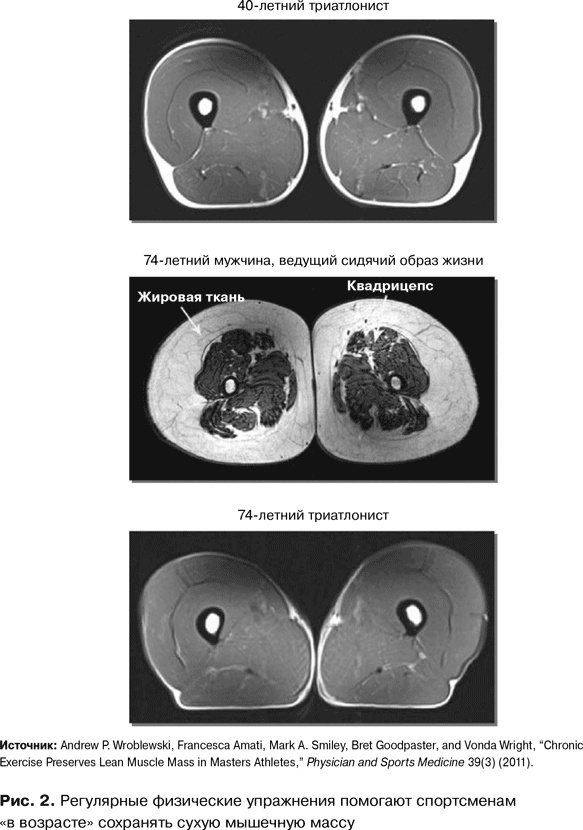

Что же происходит с мышцами, если вы регулярно и активно двигаетесь? Мы с коллегами решили ответить на этот вопрос, понаблюдав за немолодыми спортсменами-любителями, тренирующимися четыре-пять раз в неделю{8}. Благодаря снимкам МРТ я смогла отследить изменения в объемах сухой мышечной массы. Результат меня потряс.

Постоянная подвижность сохраняет сухую мышечную массу, предотвращает заплывание мышц жиром и потерю мышечной силы. Источник молодости существует, а волшебный эликсир – это подвижность! Но, как говорится, лучше один раз увидеть.

На рис. 2 представлен снимок бедра 40-летнего триатлониста. Похоже на кусок нежирной говядины. Мышцы в превосходном состоянии, мышца жиром не заплыла, подкожного жира практически нет. Далее мы видим снимок бедра 74-летнего мужчины, ведущего сидячий образ жизни. Совсем другая картина, правда? Мышцы развиты слабо, количество подкожного жира значительно, жир проник и в мышцы. Это скорее жирный ростбиф, чем постная говядина. А теперь взгляните на следующий снимок. Кульминационный момент. Мы видим бедро физически активного 70-летнего мужчины, триатлониста. Перед нами снова будто кусок нежирной говядины – отличное состояние мышц, совсем мало жира, что внутри, что вокруг. И – в качестве бонуса – видно, что квадрицепсы человека, живущего активной жизнью, с годами не теряют силы. В ходе моего исследования ни в одной возрастной группе до 60 лет не наблюдалось никакого статистически значимого расхождения в силе, а затем – никаких дополнительных различий вплоть до последней, 80-летней возрастной группы.